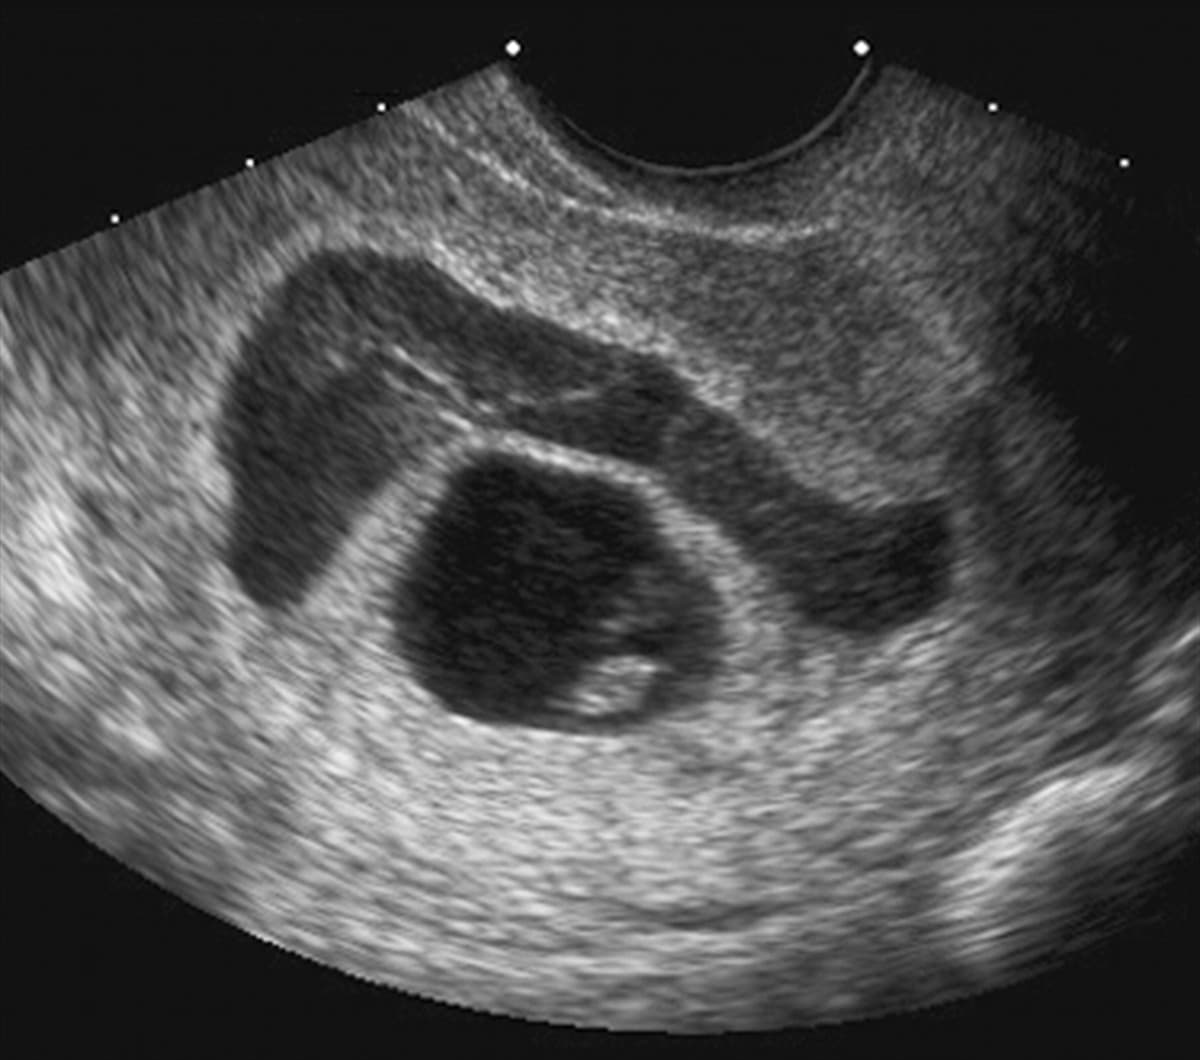

Tụ máu dưới màng đệm còn được gọi là tụ máu dưới màng nuôi, tụ dịch màng đệm hay xuất huyết dưới màng đệm. Đây là hiện tượng xuất hiện máu tụ dưới lớp màng bên ngoài túi thai, ở khu vực giữa nhau thai và tử cung bao gồm tụ máu dưới màng đệm sinh lý và tụ máu bệnh lý.

Trong khoảng 2 tuần đầu khi trứng thụ tinh bắt đầu làm tổ trong buồng tử cung tương đương với tuổi thai khoảng 4 tuần tuổi, mẹ bầu có thể bị tụ máu dưới màng đệm. Đây là hiện tượng sinh lý bình thường. Hiện tượng này thường không gây đau hay chảy máu. Mẹ bầu không nên quá lo lắng nếu phát hiện trong siêu âm.

Tụ máu dưới màng đệm bệnh lý là tình trạng xuất hiện máu tụ giữa tử cung và nhau thai do mép bánh rau bị bong hoặc các mạch xong rìa mép bánh rau bị vỡ. Hiện tượng này thường xảy ra trong ba tháng đầu tiên của thai kỳ. Đây là hiện tượng nguy hiểm, có thể đe dọa sảy thai ở mẹ bầu và cần được theo dõi sát sao.

Các dấu hiệu trên đây thường rất giống với nhiều tình trạng bệnh lý khác có thể gặp ở mẹ bầu. Chính vì thế, cách tốt nhất là khi thấy bất thường, mẹ bầu nên đến trực tiếp các cơ sở chuyên sản khoa chất lượng để được thăm khám và chẩn đoán chính xác. Để chẩn đoán tụ dịch màng đệm, các bác sĩ sẽ tiến hành siêu âm để quan sát vị trí thai nhi, túi thai và khoảng trống giữa túi thai và tử cung có xuất hiện ổ dịch hay không.